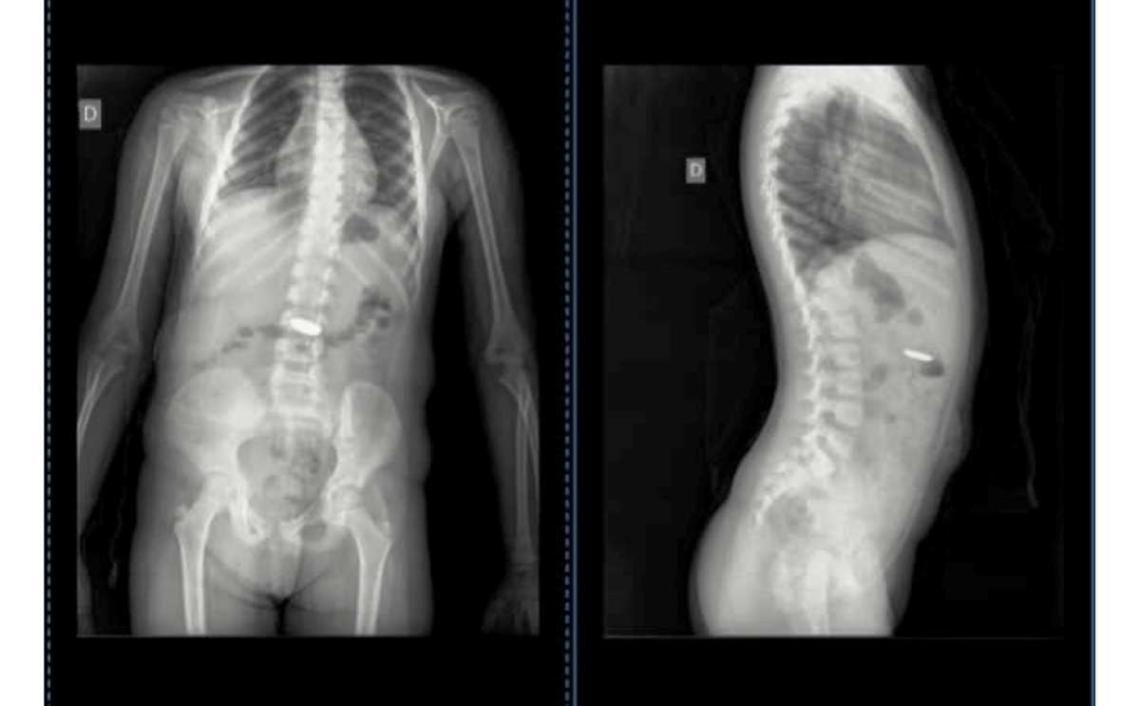

“Siete médicos en Chascomús vieron las imágenes de las radiografías que le hicimos a Isabella por el tema de la pila ‘botón’ que se tragó. ¡¡Sí, siete!! Cuatro en la Guardia y 3 por mensaje, solo uno, al que le pasé por mensaje ayer, supo ver lo que pasaba”, indicó la madre de Isabella en un posteo realizado en la madrugada de este lunes en su cuenta de Facebook.

La nena, que se había tragado la pila “botón” el jueves pasado, fue llevada al Hospital de Niños de La Plata, donde le realizaron una endoscopia y le pudieron extraer la pila. La madre dijo que “por suerte decidí hacerle caso” al Dr. Jorge Ortale que detectó la presencia del elemento extraño en la radiografía de su hija.

“Pregunto ahora: ¿de siete sólo uno vio lo que pasaba? ¿Y si esa pila seguía ahí y provocaba un mal mayor a mi hija? Desde el jueves 22/6 mi hija tenía esa pila en su estómago. Gracias Doc. Jorge Ortale, usted sí supo ver lo que pasaba”, destacó Ganuza.